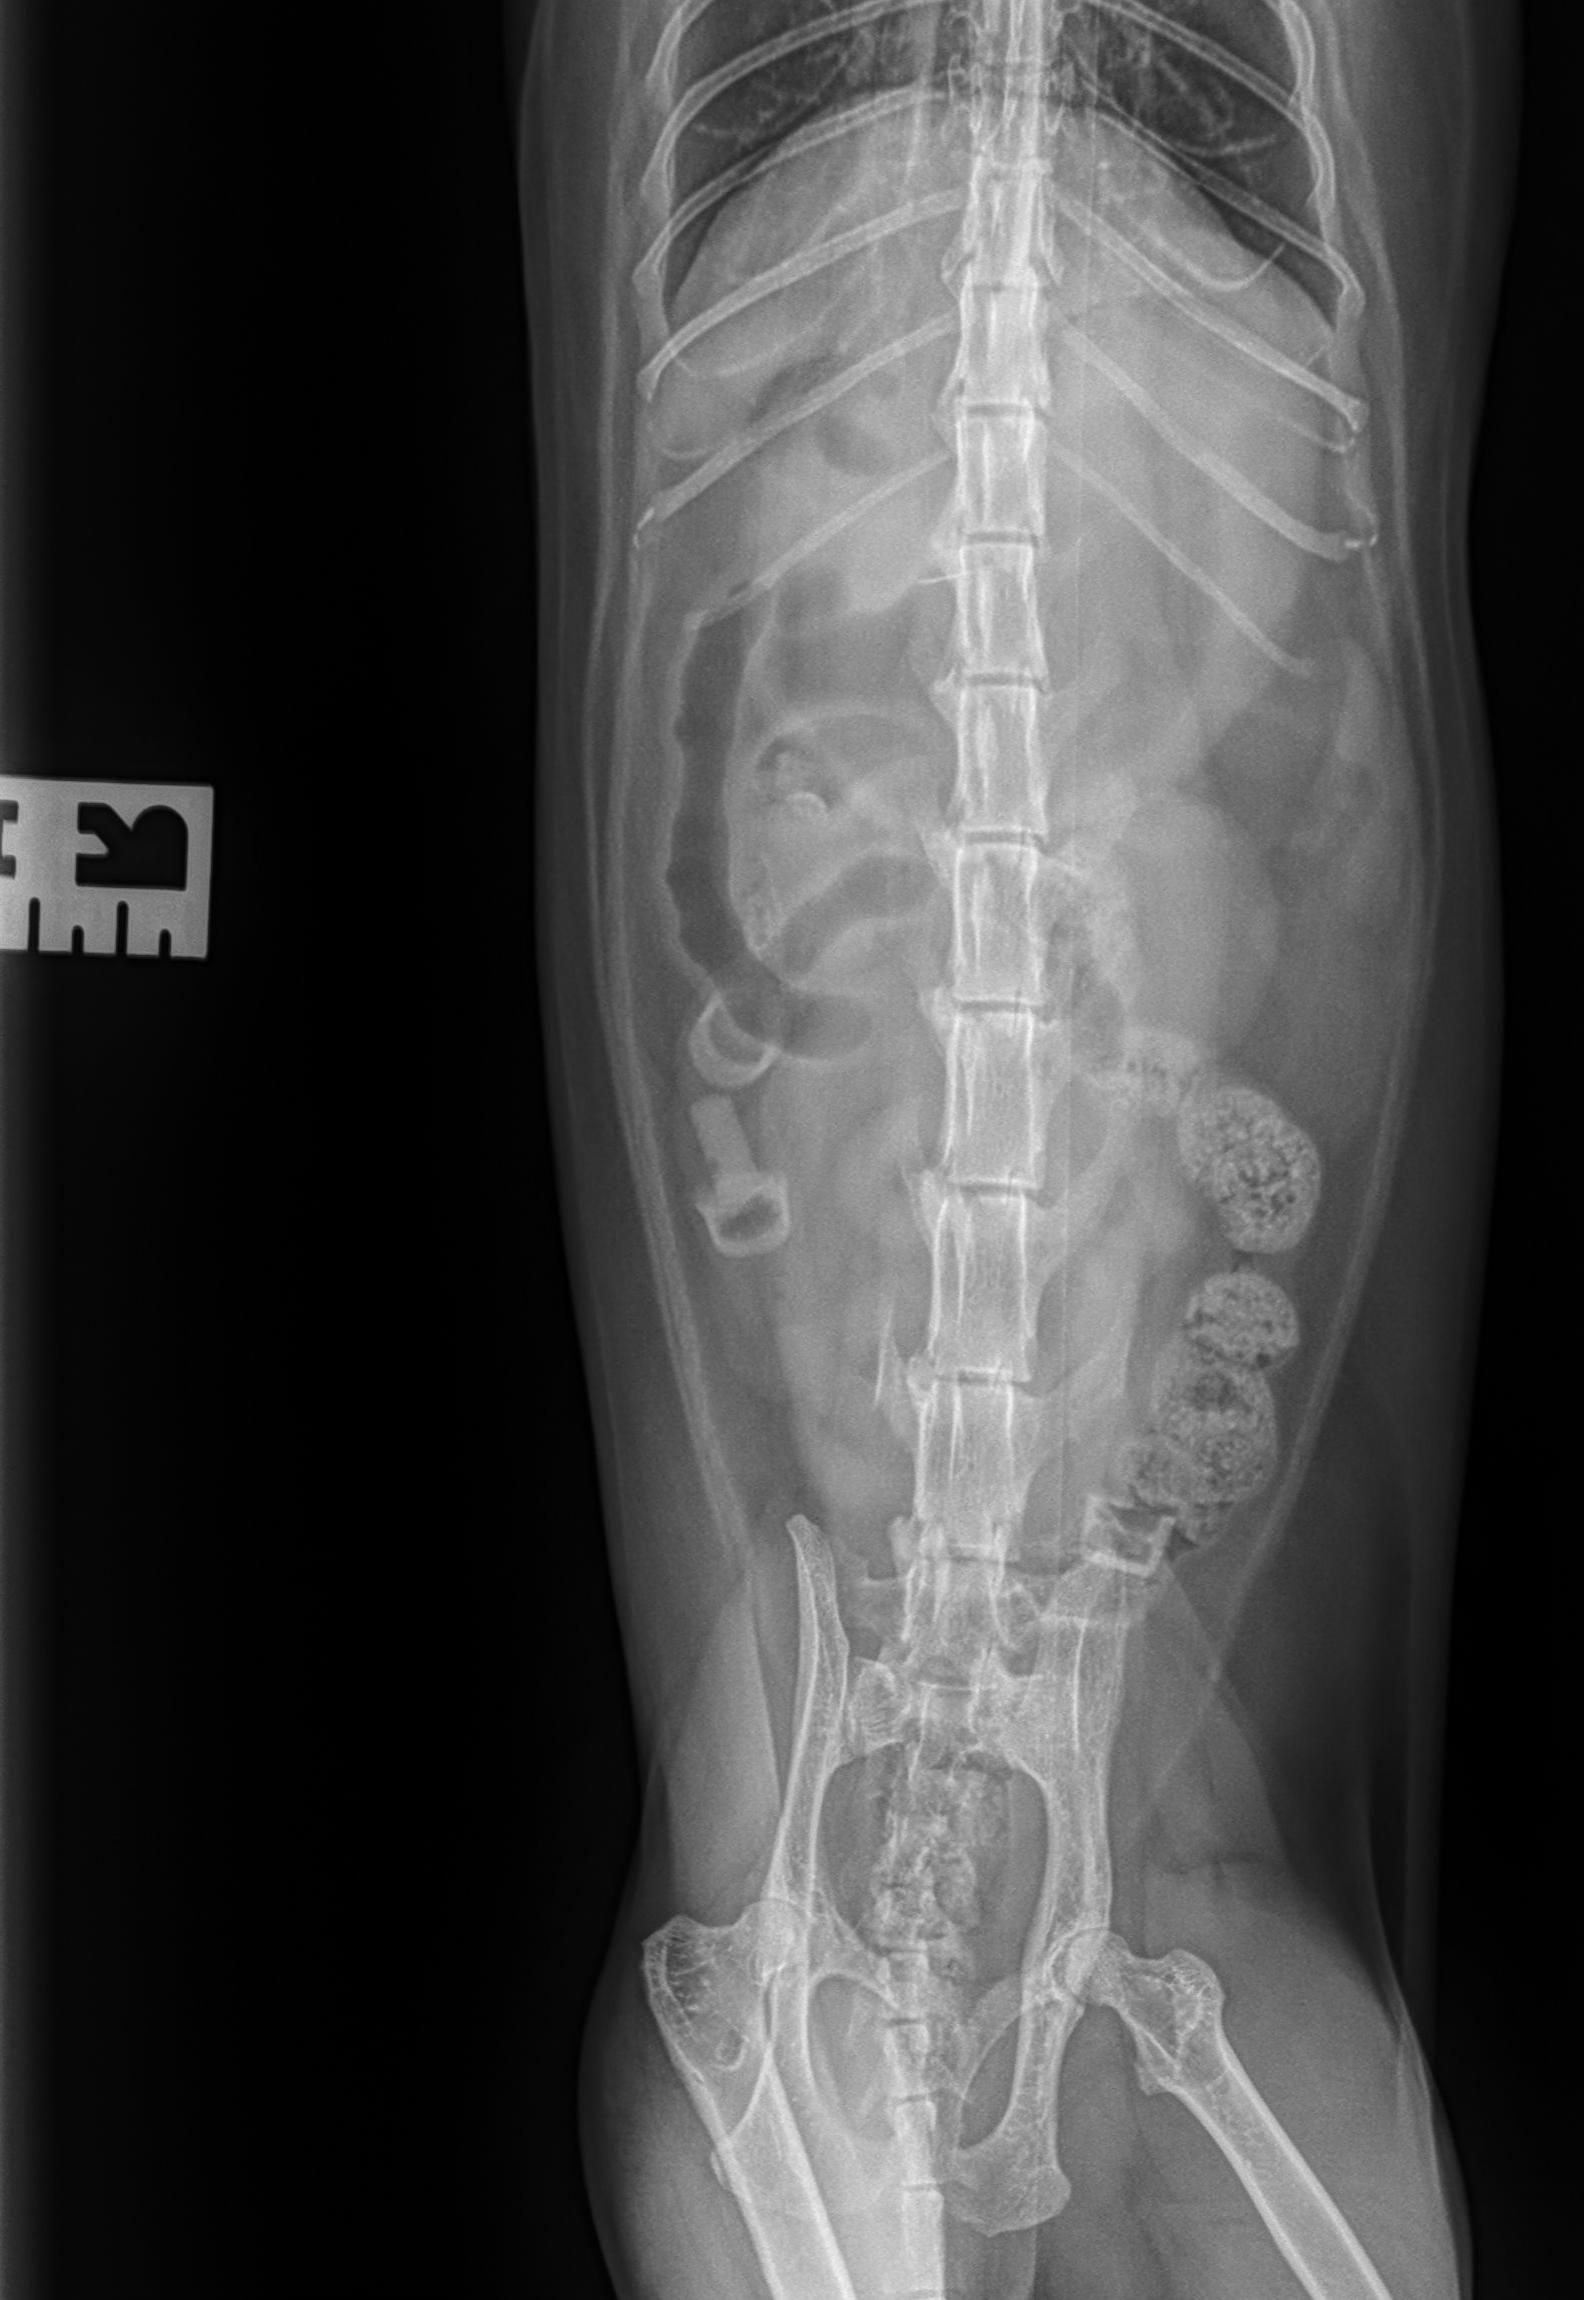

Beschrijving van de röntgenfoto's

Het serosale detail is binnen de normale grenzen. Er bevinden zich vier Nerf-kogels in het maagdarmkanaal: twee in het colon en twee in de dunne darm. Enkel het rubberachtige deel van de kogels is aanwezig en slechts één is volledig, van de overige is enkel het uiteinde zichtbaar. Er is een matige dilatatie van de maag met gas en vocht. De dunne darm is voornamelijk met vocht gevuld, met lichte gasdilatatie. De rest van het abdomen vertoont geen afwijkingen.

- Nerfgun-kogels in het maagdarmkanaal: Twee in de dikke darm, twee in de dunne darm.

- Opletten voor een mechanische obstructie, vanwege dilatatie van de maag en de dunne darm (minstens van partiële aard). De aanwezigheid van twee kogels in het colon kan echter wijzen op mogelijke spontane passage. Herhaalde abdominale radiografie en of abdominale echografie kan overwogen worden binnen 8 tot 12 uur, of eerder indien de patiënt klinisch verslechtert of niet verbetert, voor verdere evaluatie indien klinisch geïndiceerd. Als alternatief kan een chirurgische exploratie overwogen worden indien klinisch geïndiceerd.